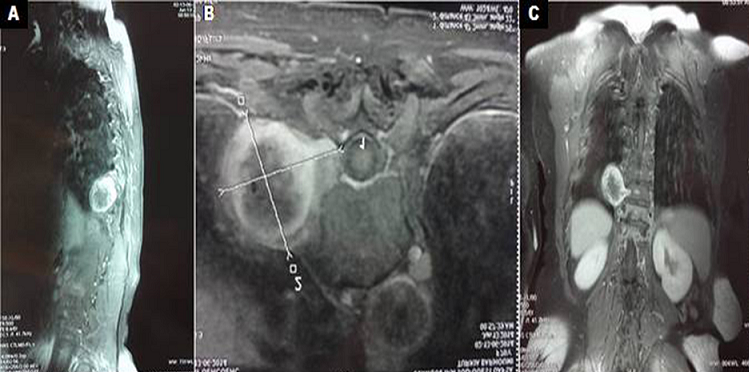

Le schwannome est une tumeur nerveuse bénigne rare. Il peut être à l'origine d'une ostéolyse mécanique des pédicules des vertèbres sus et sous jacente, lors de la croissance tumorale, pour permettre l'extension extra-rachidienne. Nous rapportons une association exceptionnelle de schwannome et de mal de pott au même niveau. Il s'agissait d'une patiente âgée de 67 ans, ayant des antécédents de diabète type 2, hospitalisée pour rachialgie lombaire, d'horaire inflammatoire évoluant depuis 3 mois, associée à un amaigrissement non chiffré, une asthénie et des sueurs nocturnes. L'examen physique trouvait une patiente subfébrile à 37,8°C, une raideur rachidienne avec une douleur provoquée à la pression des épineuses de D11-D12 et à la mobilisation du rachis. L'examen neurologique était normal. L'imagerie par résonance magnétique du rachis et de la moelle, pratiquée en urgence, montrait une spondylodiscite infectieuse D11-D12 avec une épidurite antérieure et une formation tissulaire centrée sur l'angle costo-vertébral droit de D10-D11, de signal hétérogène, en hyposignal T1. Cette masse est bien limitée de 43X47x48 mm, encapsulée, se rehaussant en périphérie après injection de produit de contraste et présentant une extension au niveau du foramen intervertébral, aspect compatible. avec un schwannome. Le bilan étiologique de la spondylodiscite avait conclu à une origine tuberculeuse. Le diagnostic de schwannome était confirmé par la biopsie percutanée sous scanner. Un traitement médical par antituberculeux était entamé et la patiente est adressée en neurochirurgie. L'association au même endroit d'un mal de pott et d'une tumeur nerveuse est exceptionnelle et pose le diagnostic différentiel avec une collection paravértébrale compliquant la spondylodiscite. La greffe du Bacille de Koch à cet endroit pourrait être expliquée par les anomalies organiques provoquées lors de l'extension tumorale.